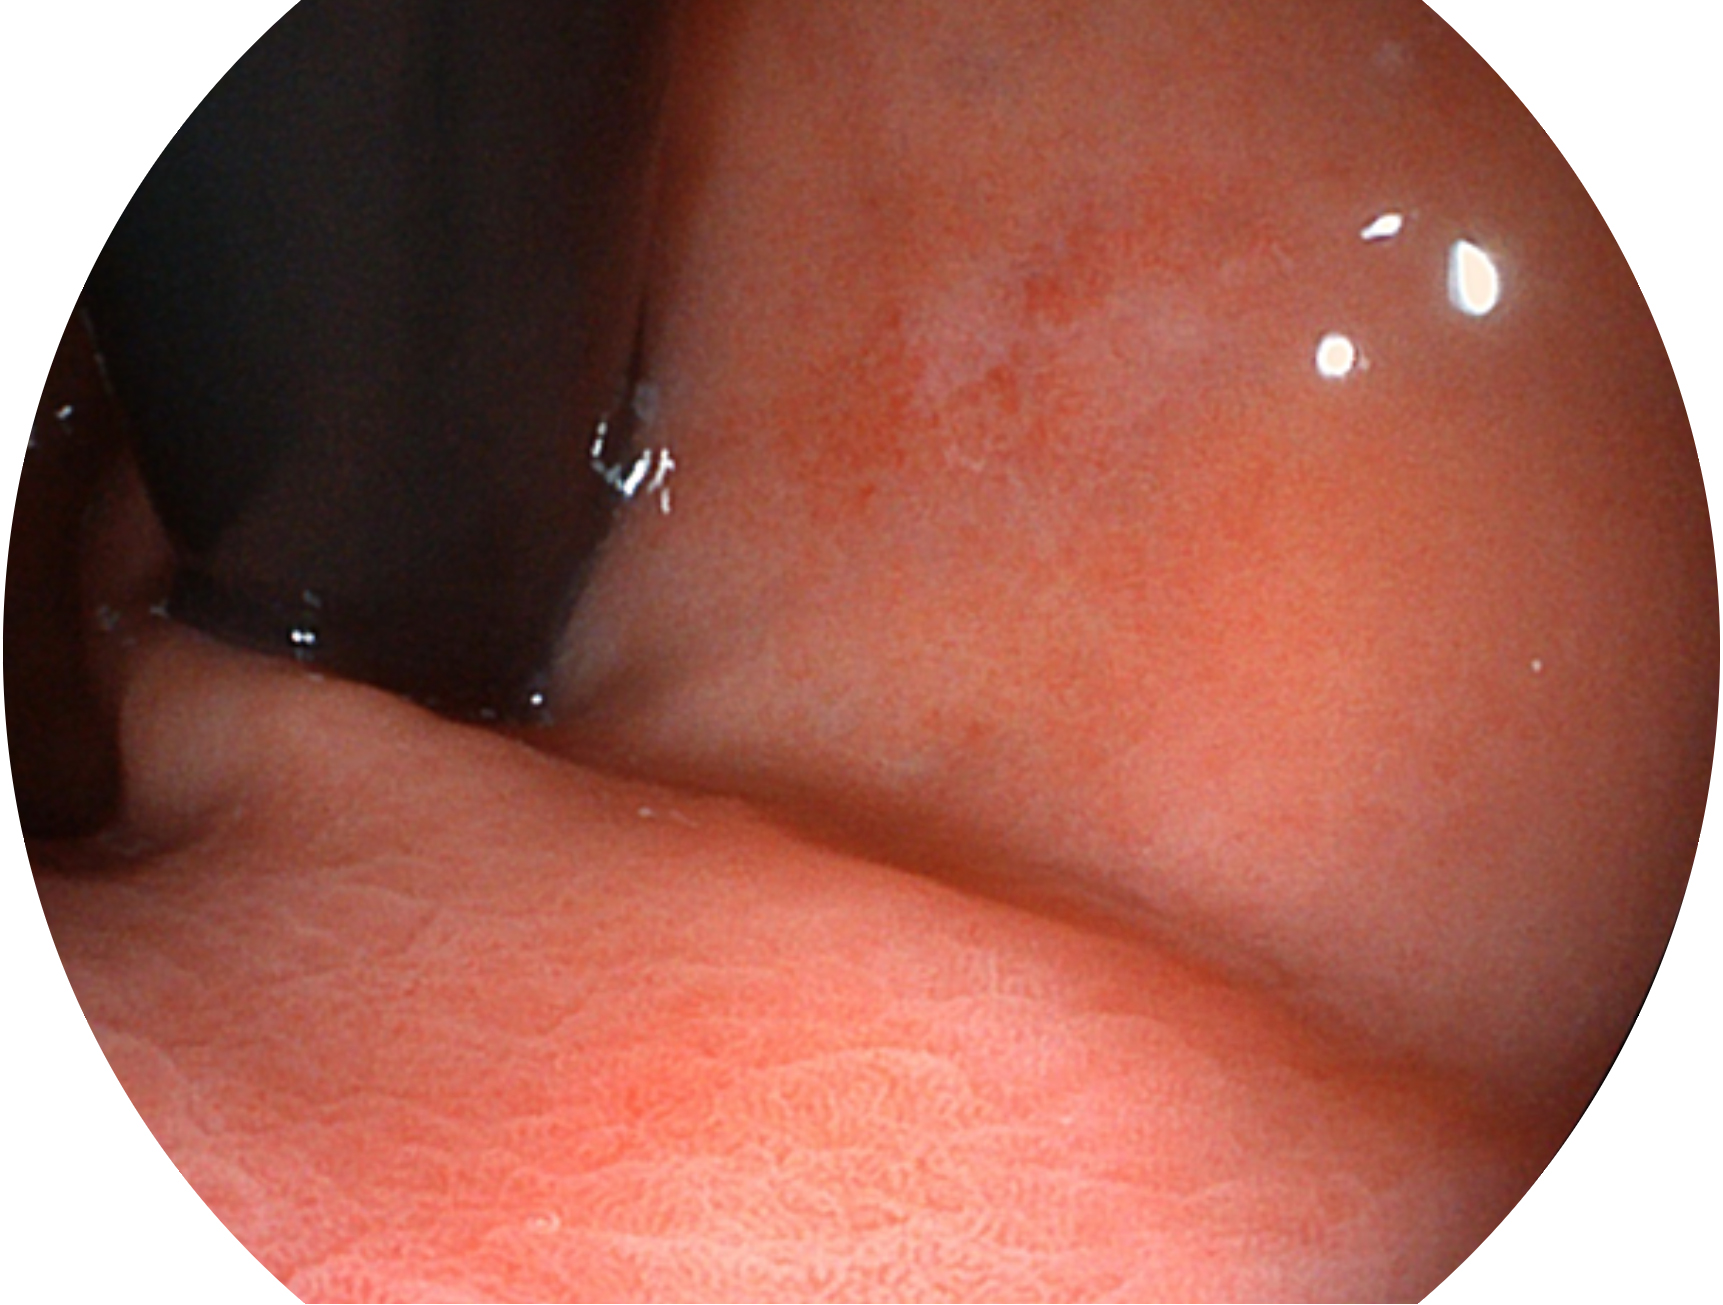

环球UG官网新开发的内镜染色技术,主要是基于多波长LED 光源的开发,VLS-55Q 四波长LED 光源是由四个不同颜色的LED光按照相应照明模式所规定的特定发光比例进行合束后形成,合束后形成的照明光的光谱由红光、绿光、蓝光及蓝紫光这四个不同的波段范围构成。具有更高光谱自由度,通过光谱比例的控制,实现了聚谱成像技术,英文全称为“Spectral Focused Imaging, SFI”,缩写为“SFI”和光电复合染色成像技术,英文全称为“Versatile Intelligent Staining Technology, VIST”,缩写为“VIST”。